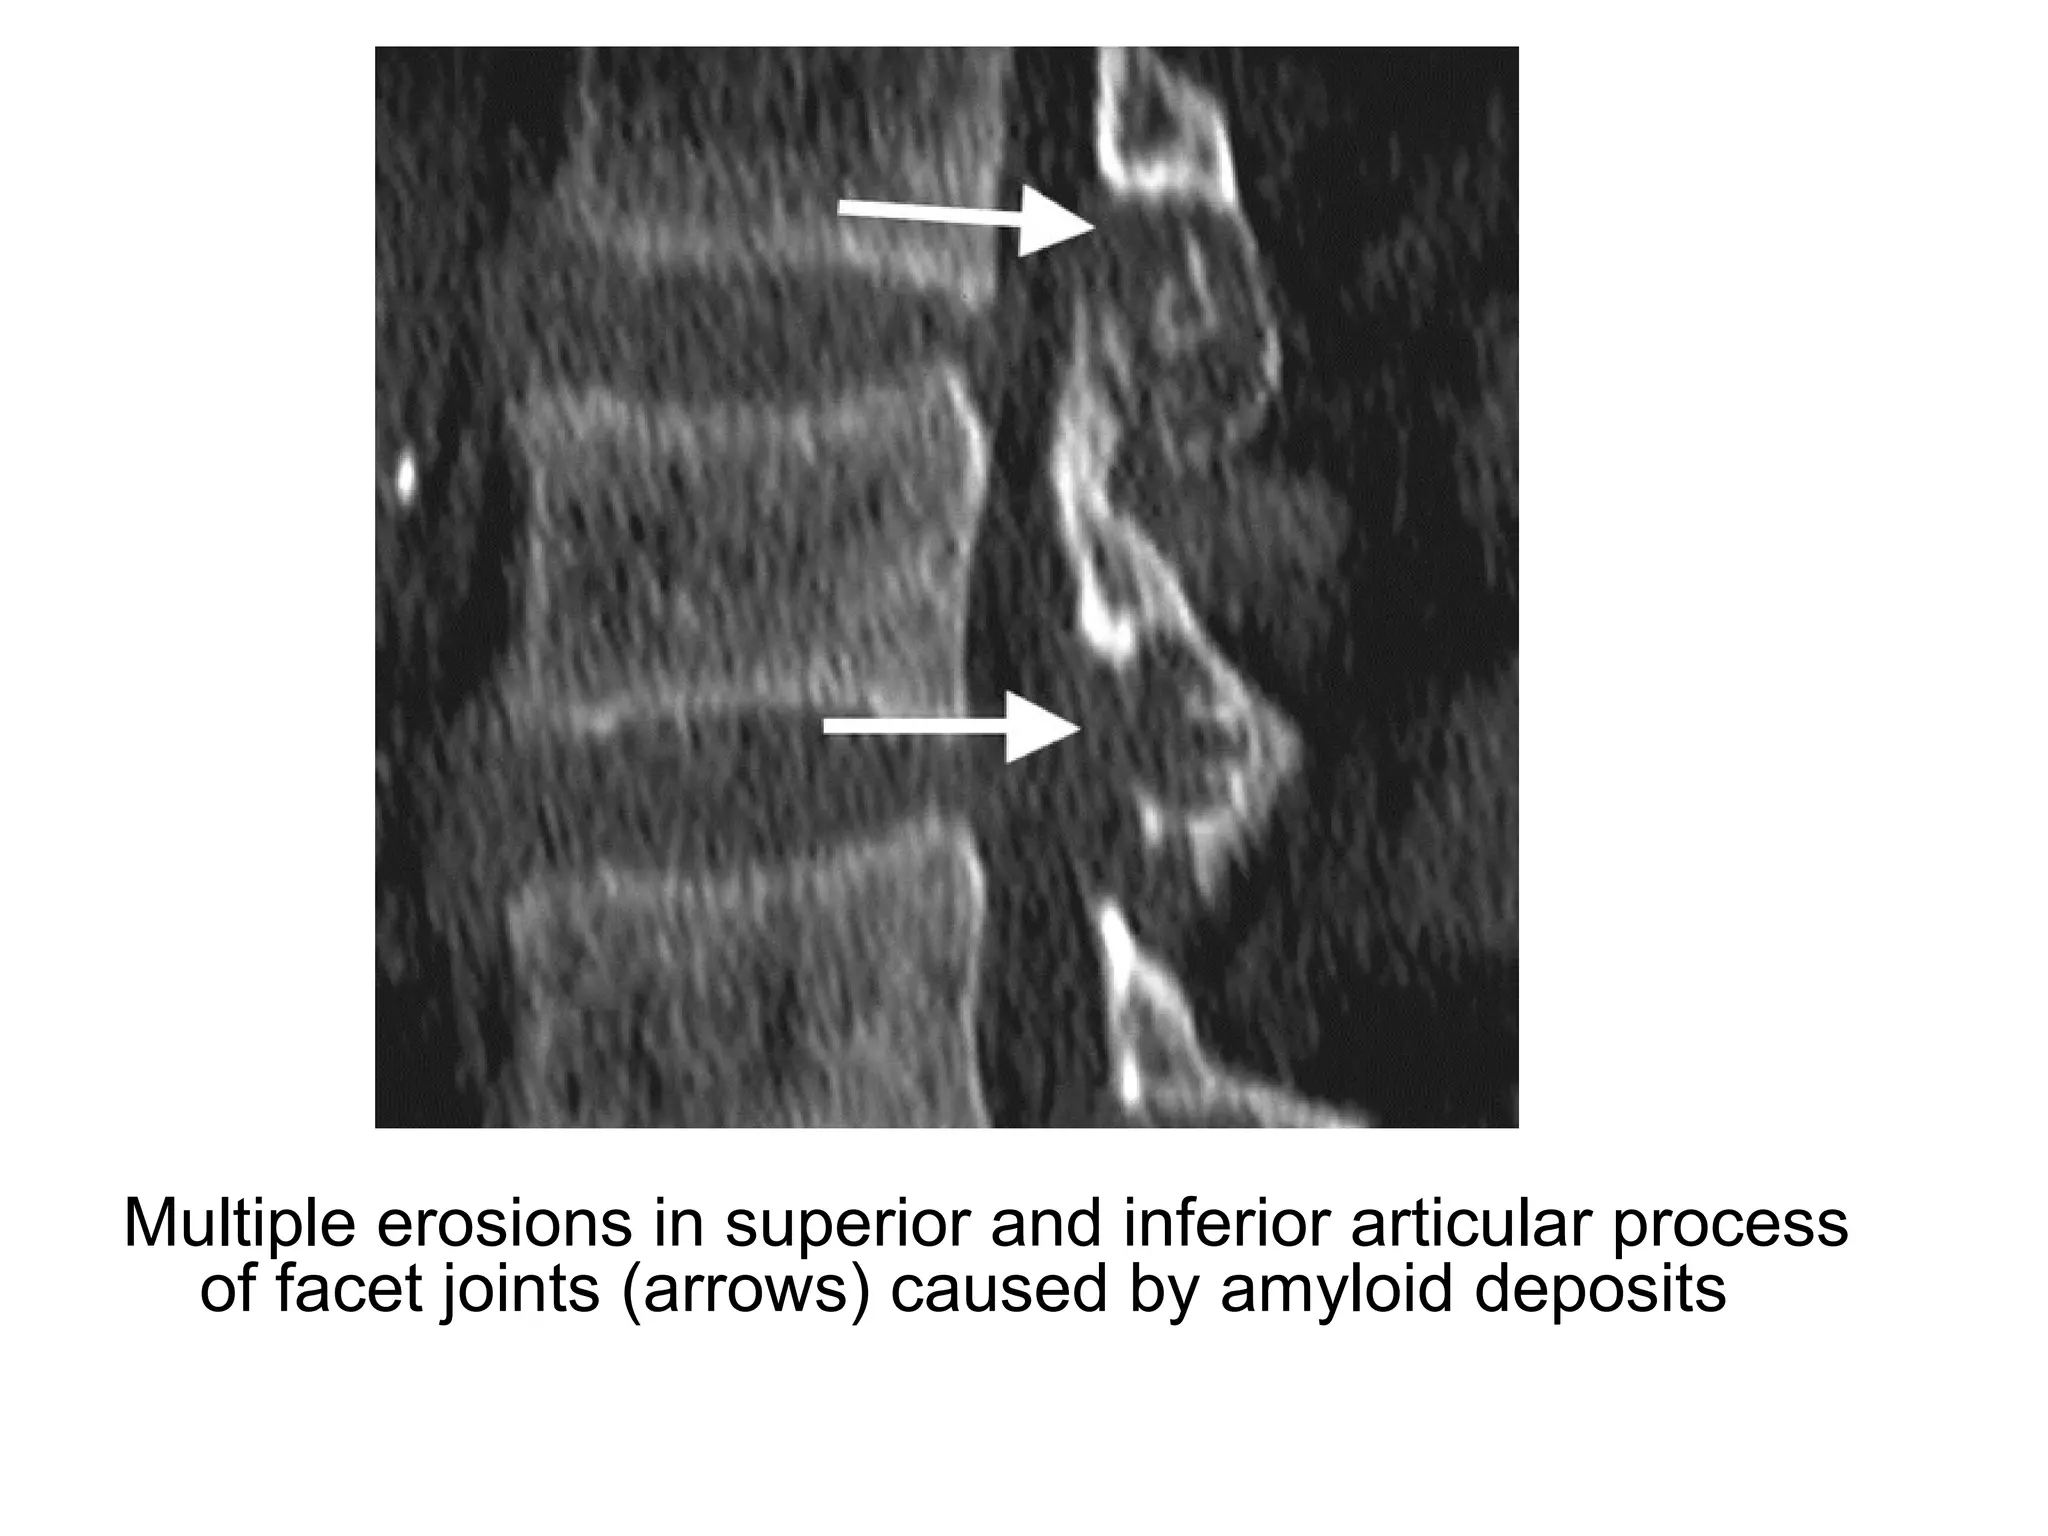

Multiple erosions in superior and inferior articular process

of facet joints (arrows) caused by amyloid deposits

Narrowing of intervertebral spaces from C2 through C7

(arrowheads)